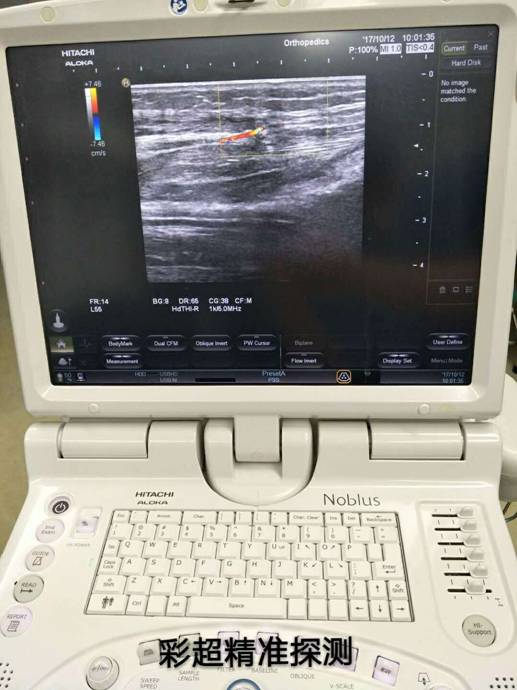

彩超定位精準治療骨折修復皮瓣

訊員萬忠波、陳平國報道:粉碎性骨折+皮膚軟組織缺損+骨(肌腱)外露等損傷有了新療法,衡陽市中心醫(yī)院采用彩超精準定位、多學科協(xié)作施術,實現(xiàn)“大手術小創(chuàng)傷”。

近一個月來,衡陽市中心醫(yī)院收治了多位外傷導致小腿多處粉碎性骨折,小腿部分皮膚軟組織缺損、骨(肌腱)外露的患者,醫(yī)院燒傷整形科、骨科、超聲科多科協(xié)作,通過施行彩超定位下,小腿穿支皮瓣轉(zhuǎn)移修復創(chuàng)面手術,均取得良好的手術效果,極大地減輕了患者的疼痛和創(chuàng)傷。

骨科根據(jù)患者骨折情況分別施行骨折復位+內(nèi)(外)固定術,然后由燒傷整形科根據(jù)患者皮膚軟組織缺損情況,制定小腿穿支皮瓣轉(zhuǎn)移修復創(chuàng)面方案。為保證手術成功率,燒傷整形科會同超聲科由黃道遠主任于術前利用彩超精準的探測小腿術區(qū)的各個動脈穿刺,并逐一標記,再由燒傷整形科手術團隊根據(jù)動脈穿支的分布情況設計皮瓣,施行小腿穿支皮瓣轉(zhuǎn)移修復術。

由于采用了彩超定位技術,使得皮瓣設計方案更合理,手術操作更精準,手術耗時更少,更因為保護好了血管,術后皮瓣腫脹,存活均較以往有明顯改善,手術效果得到極大保障,患者滿意度大大提高。